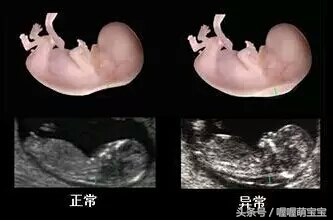

第2次B超检查应在妊娠20~25周:怀孕中期的B超检查可帮助准妈妈了解胎儿的生长发育情况,还能对胎儿的位置及羊水量有进一步的了解。还可以早期发现胎儿畸形,如胎儿的肢体畸形、唇腭裂畸形等。

当妊娠周数与腹部大小不符时,也要做B超以了解胎儿的发育情况,观察是否发生胎停育。